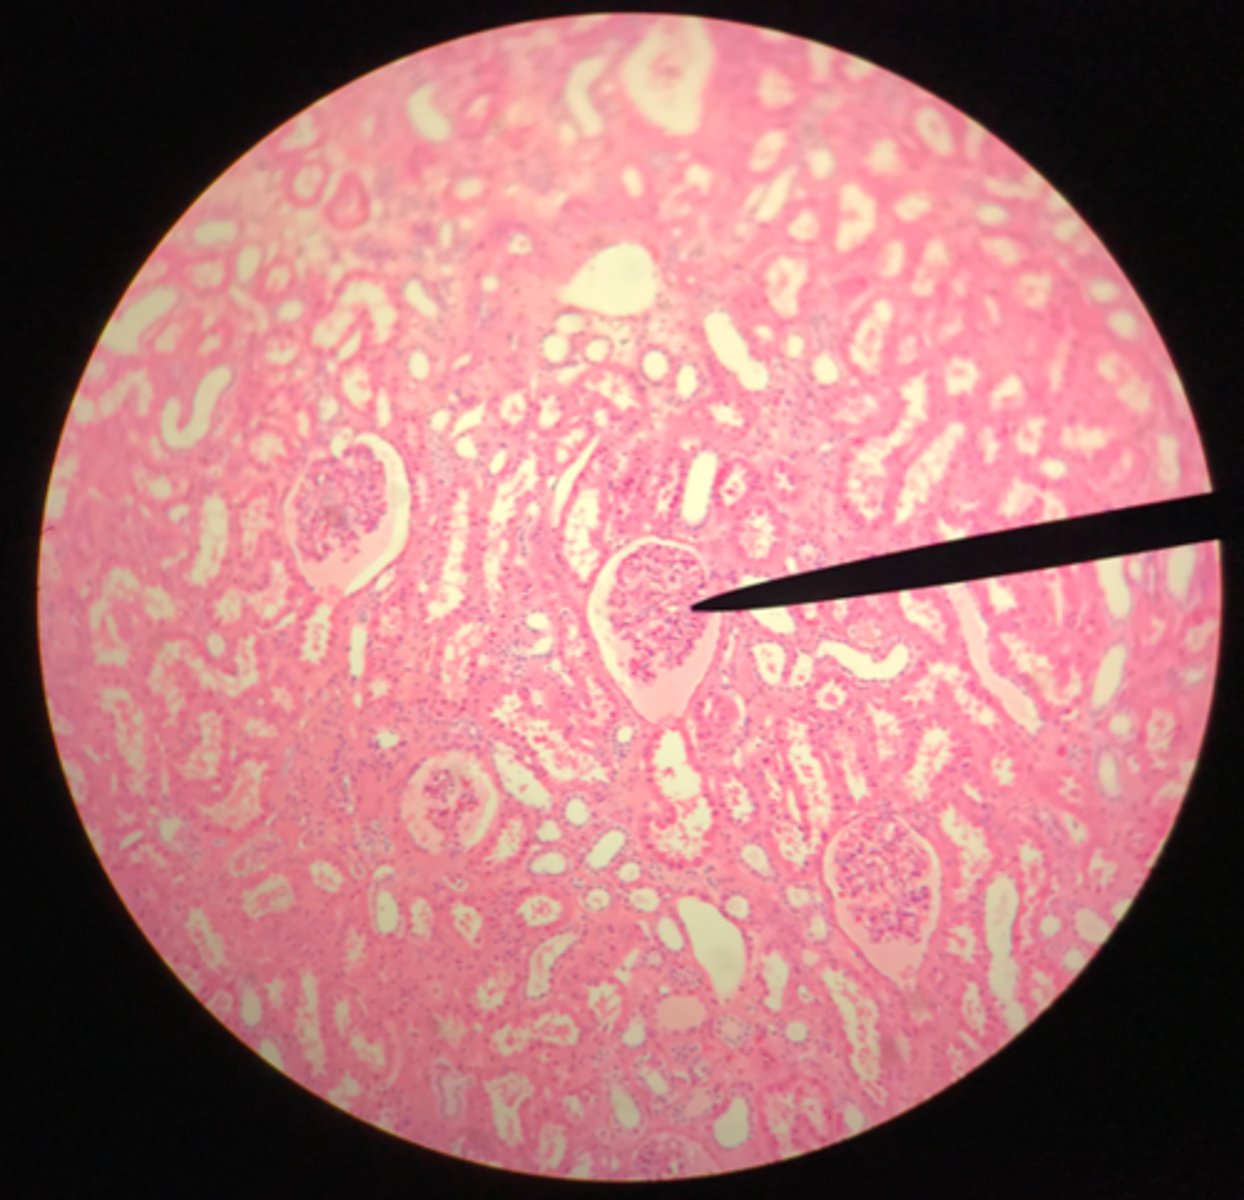

Cortex of the kidney

There are glomerular corpuscles present in the cortex. They are not present in the medulla

What layer of tissue of which organ is depicted on this slide? How can you tell?

Glomerular (Bowman's) capsule (in the cortex)

What structure of the kidney is the blue arrow pointing at?

Glomerulus

What structure of the kidney is the pointer placed on?

Renal tubules (in the cortex)

What structure of the kidney is the blue arrow pointing at?